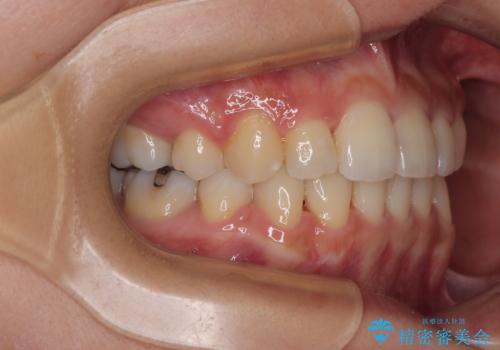

- 前歯のクロスバイトと口元の膨らんだ横顔の印象を気にして来院された患者様です。

ご本人の気にされている口元は、分析数値からするとそれほど突出しているものではありませんでした。

しかしながら。そのまま叢生を解消すると横顔が突出した印象になる可能性が高かったため、上下左右の小臼歯4本を抜歯して、ワイヤー装置にて矯正治療を行うこととしました。